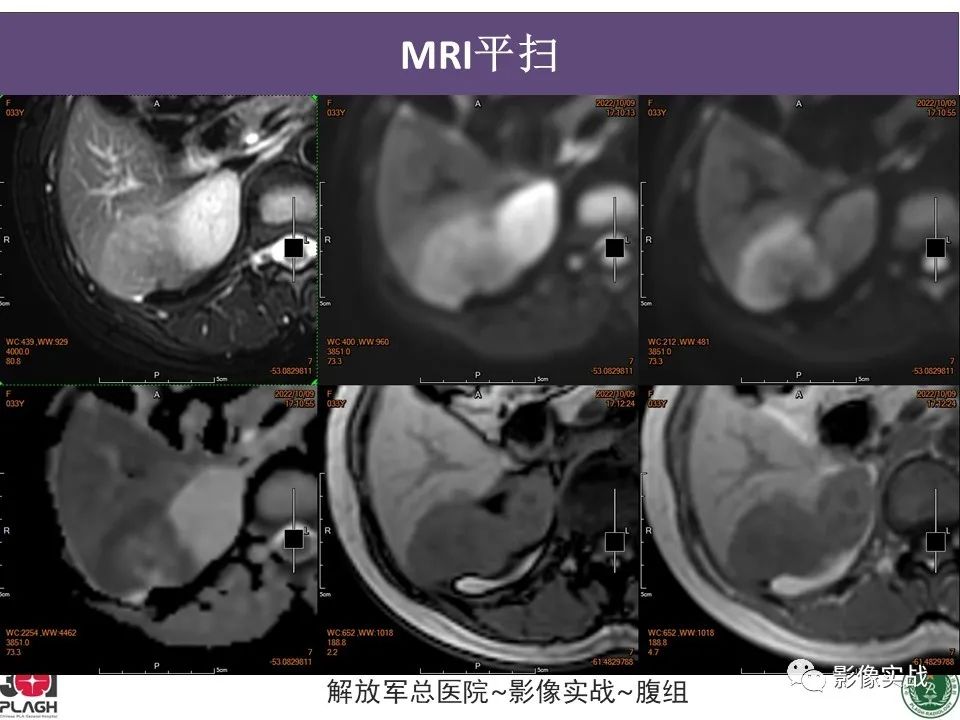

【病例】肝内胆管细胞癌1例MR影像-1

【病例】肝内胆管细胞癌1例MR影像-2